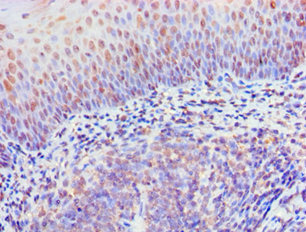

Immunohistochemistry of paraffin-embedded human tonsil tissue using CSB-PA897497ESR1HU at dilution of 1:100